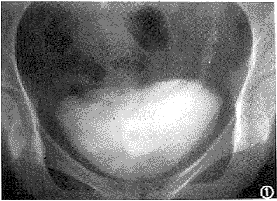

图1 排泄性尿路造影显示左侧输尿管下端囊状扩张向膀胱内突出,呈“蛇头”样 图2 同一病例,CT增强扫描,左侧输尿管下端囊状扩张并疝入膀胱内,其壁呈环形低密度影

CT平扫有时不易分辨出囊肿的真正轮廓,增强扫描显示充盈造影剂的输尿管下端呈囊状扩张;连续层面显示扩张的囊状输尿管疝入膀胱内,其壁呈环形低密度影(图2)。